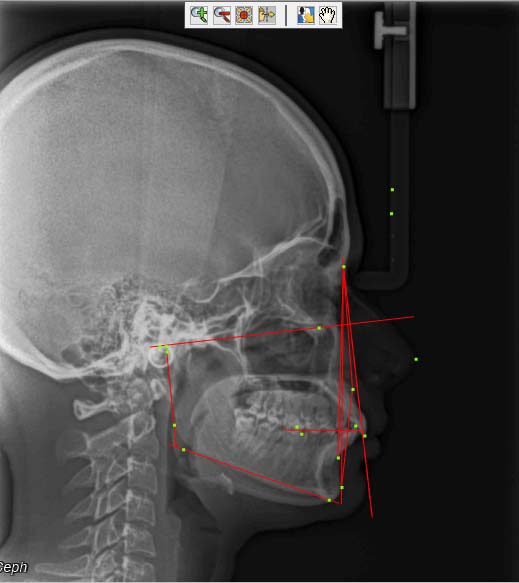

All these parameters were digitized on the photographs and lateral cephalograms using the Software. The results of the various parameters used in the study were obtained for each lateral cephalogram and photograph [Table/Fig-6,7,8 and 9]. These results were later exported and saved on MS Excel sheet.

Digitizing the lateral cephalogram using Dolphin Software.

Measurements of all the parameters on the lateral cephalogram using Dolphin Software. (Images left to right)